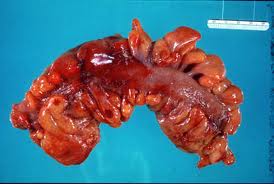

DIVERTICULITIS DEL COLON

El colon es el sitio más común de formación de divertículos en el tubo digestivo. Cuando los divertículos no están inflamados, el proceso se conoce por diverticulosis; cuando se añade inflamación, se usa entonces el término diverticulitis. Estas “herniaciones mucosas” se desarrollan en los puntos débiles de la pared del colon bajo el influjo de la presión intraluminal aumentada. El estreñimiento ha sido citado con frecuencia como un factor importante que aumenta la presión intracolónica.

La enfermedad diverticular con pocos síntomas y sin complicaciones puede tratarse sin cirugía, a base de dieta adecuada y laxantes suaves.  Las complicaciones que pueden presentarse ante esta enfermedad son la Hemorragia, la obstrucción intestinal y la diverticulitis. Esta última varía desde un ataque moderado asociado con dolor en fosa iliaca izquierda, fiebre, y estreñimiento, hasta una enfermedad más dramática que requiere hospitalización inmediata. La mayoría de los pacientes admitidos a los hospitales responden a los antibióticos y ayuno. Después de la recuperación, la mayoría de estos pacientes permanecen bien sin un nuevo cuadro posterior. Sin embargo, algunos de ellos continúan teniendo síntomas, los cuales pueden ser tan importantes o muy frecuentes por lo que requieren tratamiento quirúrgico electivo.